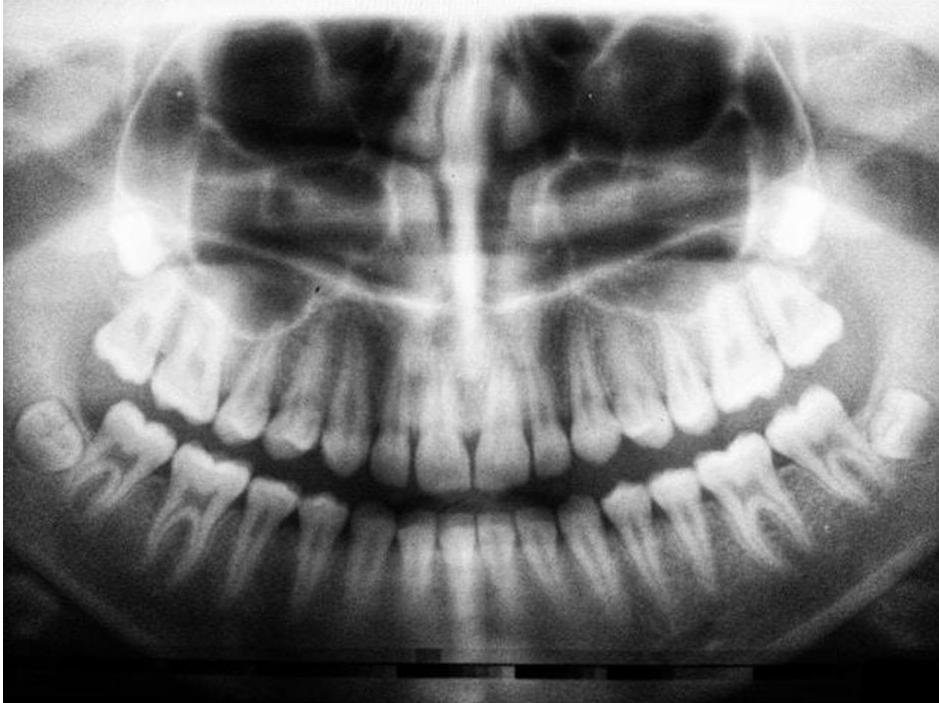

Le protesi dentali, comunemente note come dentiere, sono dispositivi protesici utilizzati per sostituire i denti mancanti. Possono essere totali o parziali, a seconda del numero di denti da sostituire, e sono personalizzate per adattarsi alla bocca del paziente. Le protesi dentali possono aiutare a mantenere la forma del viso, a migliorare la masticazione e la digestione, a promuovere la corretta fonetica e a ridare fiducia nel sorriso.

Ci sono molte ragioni per cui potrebbe essere necessario considerare l’uso di protesi dentali. I problemi di salute orale come la malattia parodontale avanzata, la carie dentale estesa o gli incidenti che causano la perdita dei denti possono richiedere l’uso di protesi. A volte, nonostante i migliori sforzi per mantenere una buona igiene orale, l’età o le condizioni mediche possono portare alla perdita dei denti. In questi casi, le protesi dentali rappresentano una soluzione pratica ed efficace.